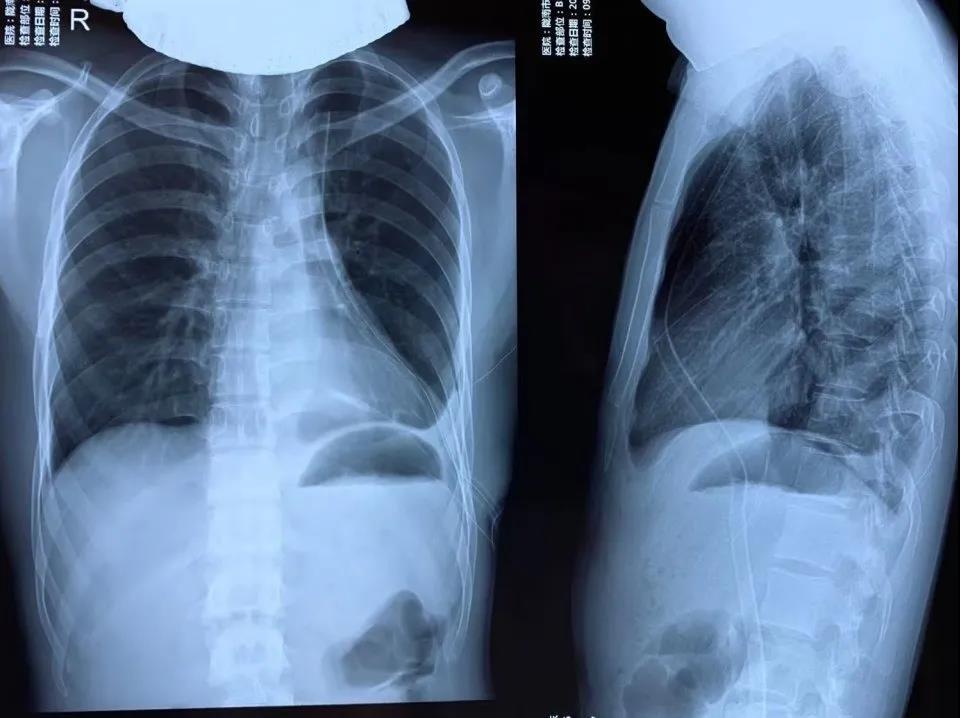

患者青年男性,半年前在外院体检时发现左肺下叶有一直径约0.8cm的部分实性结节影,11月来我院复查见结节较前增大至1.3cm,呈混合实性影,位置较深,经廖虎及胸外科医师会诊讨论后,决定为患者实施胸腔镜下左肺下叶切除术。

11月21日,手术在胸外科主任尹义学的协调下、在副教授廖虎指导下,由我院胸外科副主任医师司亮主刀,术程顺利,术后患者安返ICU。